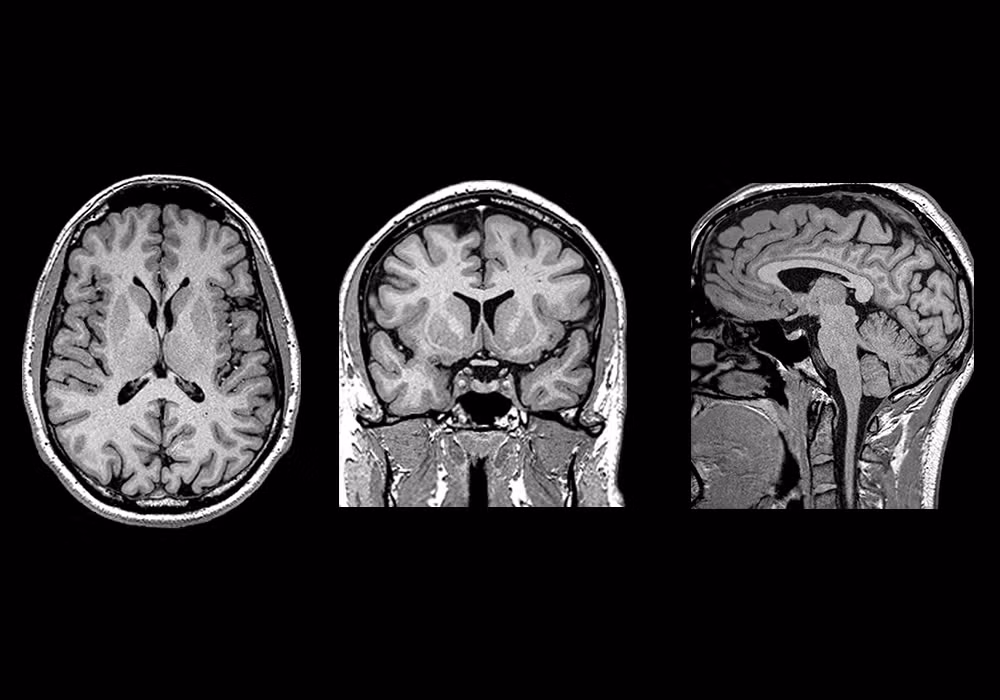

Giới khoa học Trung Quốc đã công bố kế hoạch xây dựng một máy quét não cấp độ khủng khiếp, được đánh giá là mạnh nhất thế giới hiện nay. Máy này có khả năng tích tụ từ trường cực mạnh, giúp lần đầu tiên trong lịch sử dựng lại hoạt động của toàn bộ các neuron thần kinh trong bộ não người đang sống.

Đây là một thiết bị chụp cộng hưởng từ (MRI) mạnh nhất, không chỉ làm tốt những gì công nghệ hiện nay đang làm mà còn cho phép theo dõi các phân tử hóa học trong não như natri, phốt-pho, và kali. Dự án sẽ tiêu tốn hàng tỉ Nhân dân tệ và được dự đoán mang lại "cuộc cách mạng trong lĩnh vực nghiên cứu não bộ".

Máy MRI mà Trung Quốc dự định chế tạo sẽ tạo ra từ trường lên tới 14 tesla, đủ mạnh để kích thích các hạt nhân của phân tử nặng hơn như natri, phốt-pho và kali, giúp chụp được hoạt động của não bộ.

Một tế bào neuron thần kinh có đường kính khoảng 4 - 100 micromet, nhưng máy MRI mạnh nhất hiện nay chỉ có thể quan sát được vật thể đường kính nhỏ hơn 1000 micromet. Nếu dự án thành công, vật thể nhỏ cỡ 1 micromet cũng có thể quan sát được.